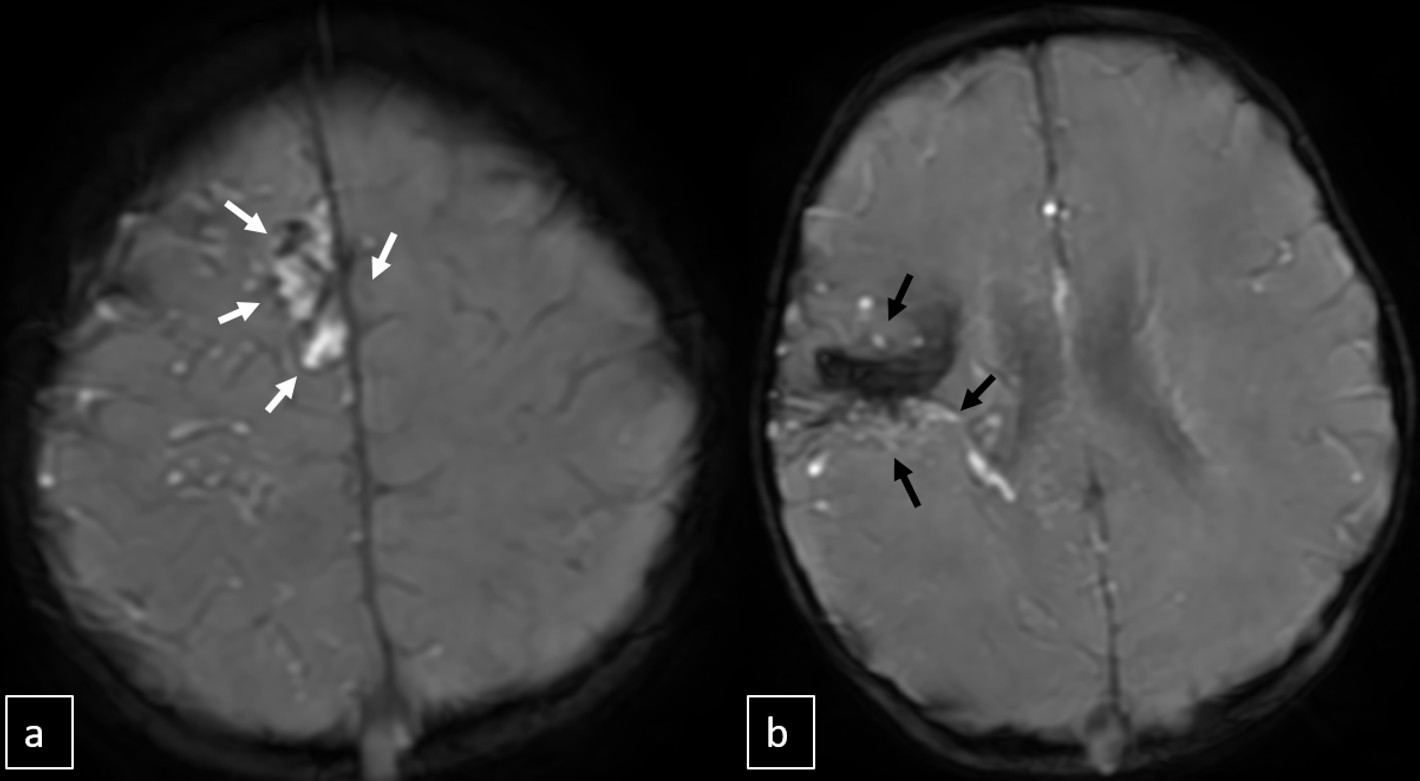

Cranial MRI demonstrated a dilated tortuous arteriovenous malformation in the right frontal lobe, fed by the distal branches of the anterior cerebral artery (ACA), draining into the cortical veins and central nervous system. A second AVM was detected in the corona radiata, with dilated parietotemporal draining veins fed by perisylvian branches of the middle cerebral artery (MCA), draining into the internal cerebral veins and the straight sinus via pericallosal dilated venous structures (Figure 2, Figure 3, Figure 4). At the level of the basal ganglia and mesencephalon, arterial angiomatosis resembling the classic “moyamoya” appearance was observed (Figure 5).

Digital subtraction angiography (DSA) confirmed the presence of two AVMs: one fed by distal branches of the right ACA and draining into the superior sagittal sinus, and another fed by MCA branches, draining into the internal cerebral vein. Capillary anastomoses were noted between the two AVMs. Selective bilateral internal carotid artery (ICA) injections revealed globally abnormal, tortuous arteriolar networks with delayed capillary filling, more pronounced on the right side (Figures 5, Figure 6, Figure 7). Based on these findings and the revised 2021 diagnostic criteria, the patient was diagnosed with MMD—characterized by stenosis of the intracranial ICA, narrowing at the terminal portion, and the development of abnormal collateral networks in the basal ganglia and periventricular white matter.4